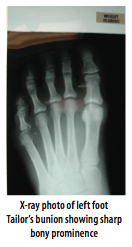

Surgical correction of your Tailor’s bunion head may be required when it is painful such that it X-ray photo of left foot Tailor’s bunion showing sharp interferes with normal daily activity, or there bony prominence are footwear fitting difficulties.